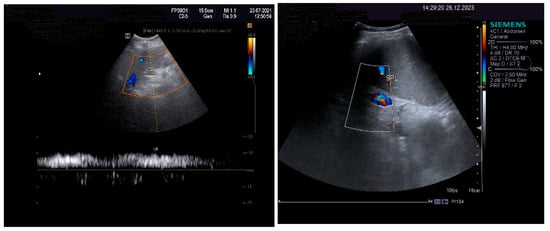

The pulsed Doppler ultrasound revealed a patency of the main portal vein as well as of the left and right portal branches and decreased, demodulated hepatopetal portal venous flow, with mildly decreased respiratory variability in the amplitude of the portal vein flow. The Dopler aspects of the liver and spleen are illustrated in Figure 4.

An important role in the imaging diagnostic approach of SOS/VOD is played by ultrasonography. According to some studies, it seems that ascites and gallbladder wall edema represent independent predictors in SOS/VOD diagnosis. Some authors reported that the thickness of the gallbladder wall correlated well with the HVPG. This particular aspect of the markedly thickened GB wall was also observed in the presented patient, associated with ascites and increase in the HVPG. Pulsed Doppler ultrasound is also useful for suggesting SOS/VOD, based on the study of the venous portal flow, which can be decreased or reversed. A significant increase in the HARI may also be associated with liver injury. Hepatic and portal flow anomalies revealed by duplex examination seem to correlate with the HVPG. However, as we have also noted, the reversed portal venous flow is not always recorded and, therefore, one cannot exclude SOS/VOD based on the absence of the hepatofugal portal flow sign [28]. The patient that we have presented in this case report displayed no reversed portal venous flow, but increased values of the HARI.

Figure 4. Doppler examination. Liver: pulsed Doppler of the portal vein (left). Spleen: color Doppler of splenic vein (right).